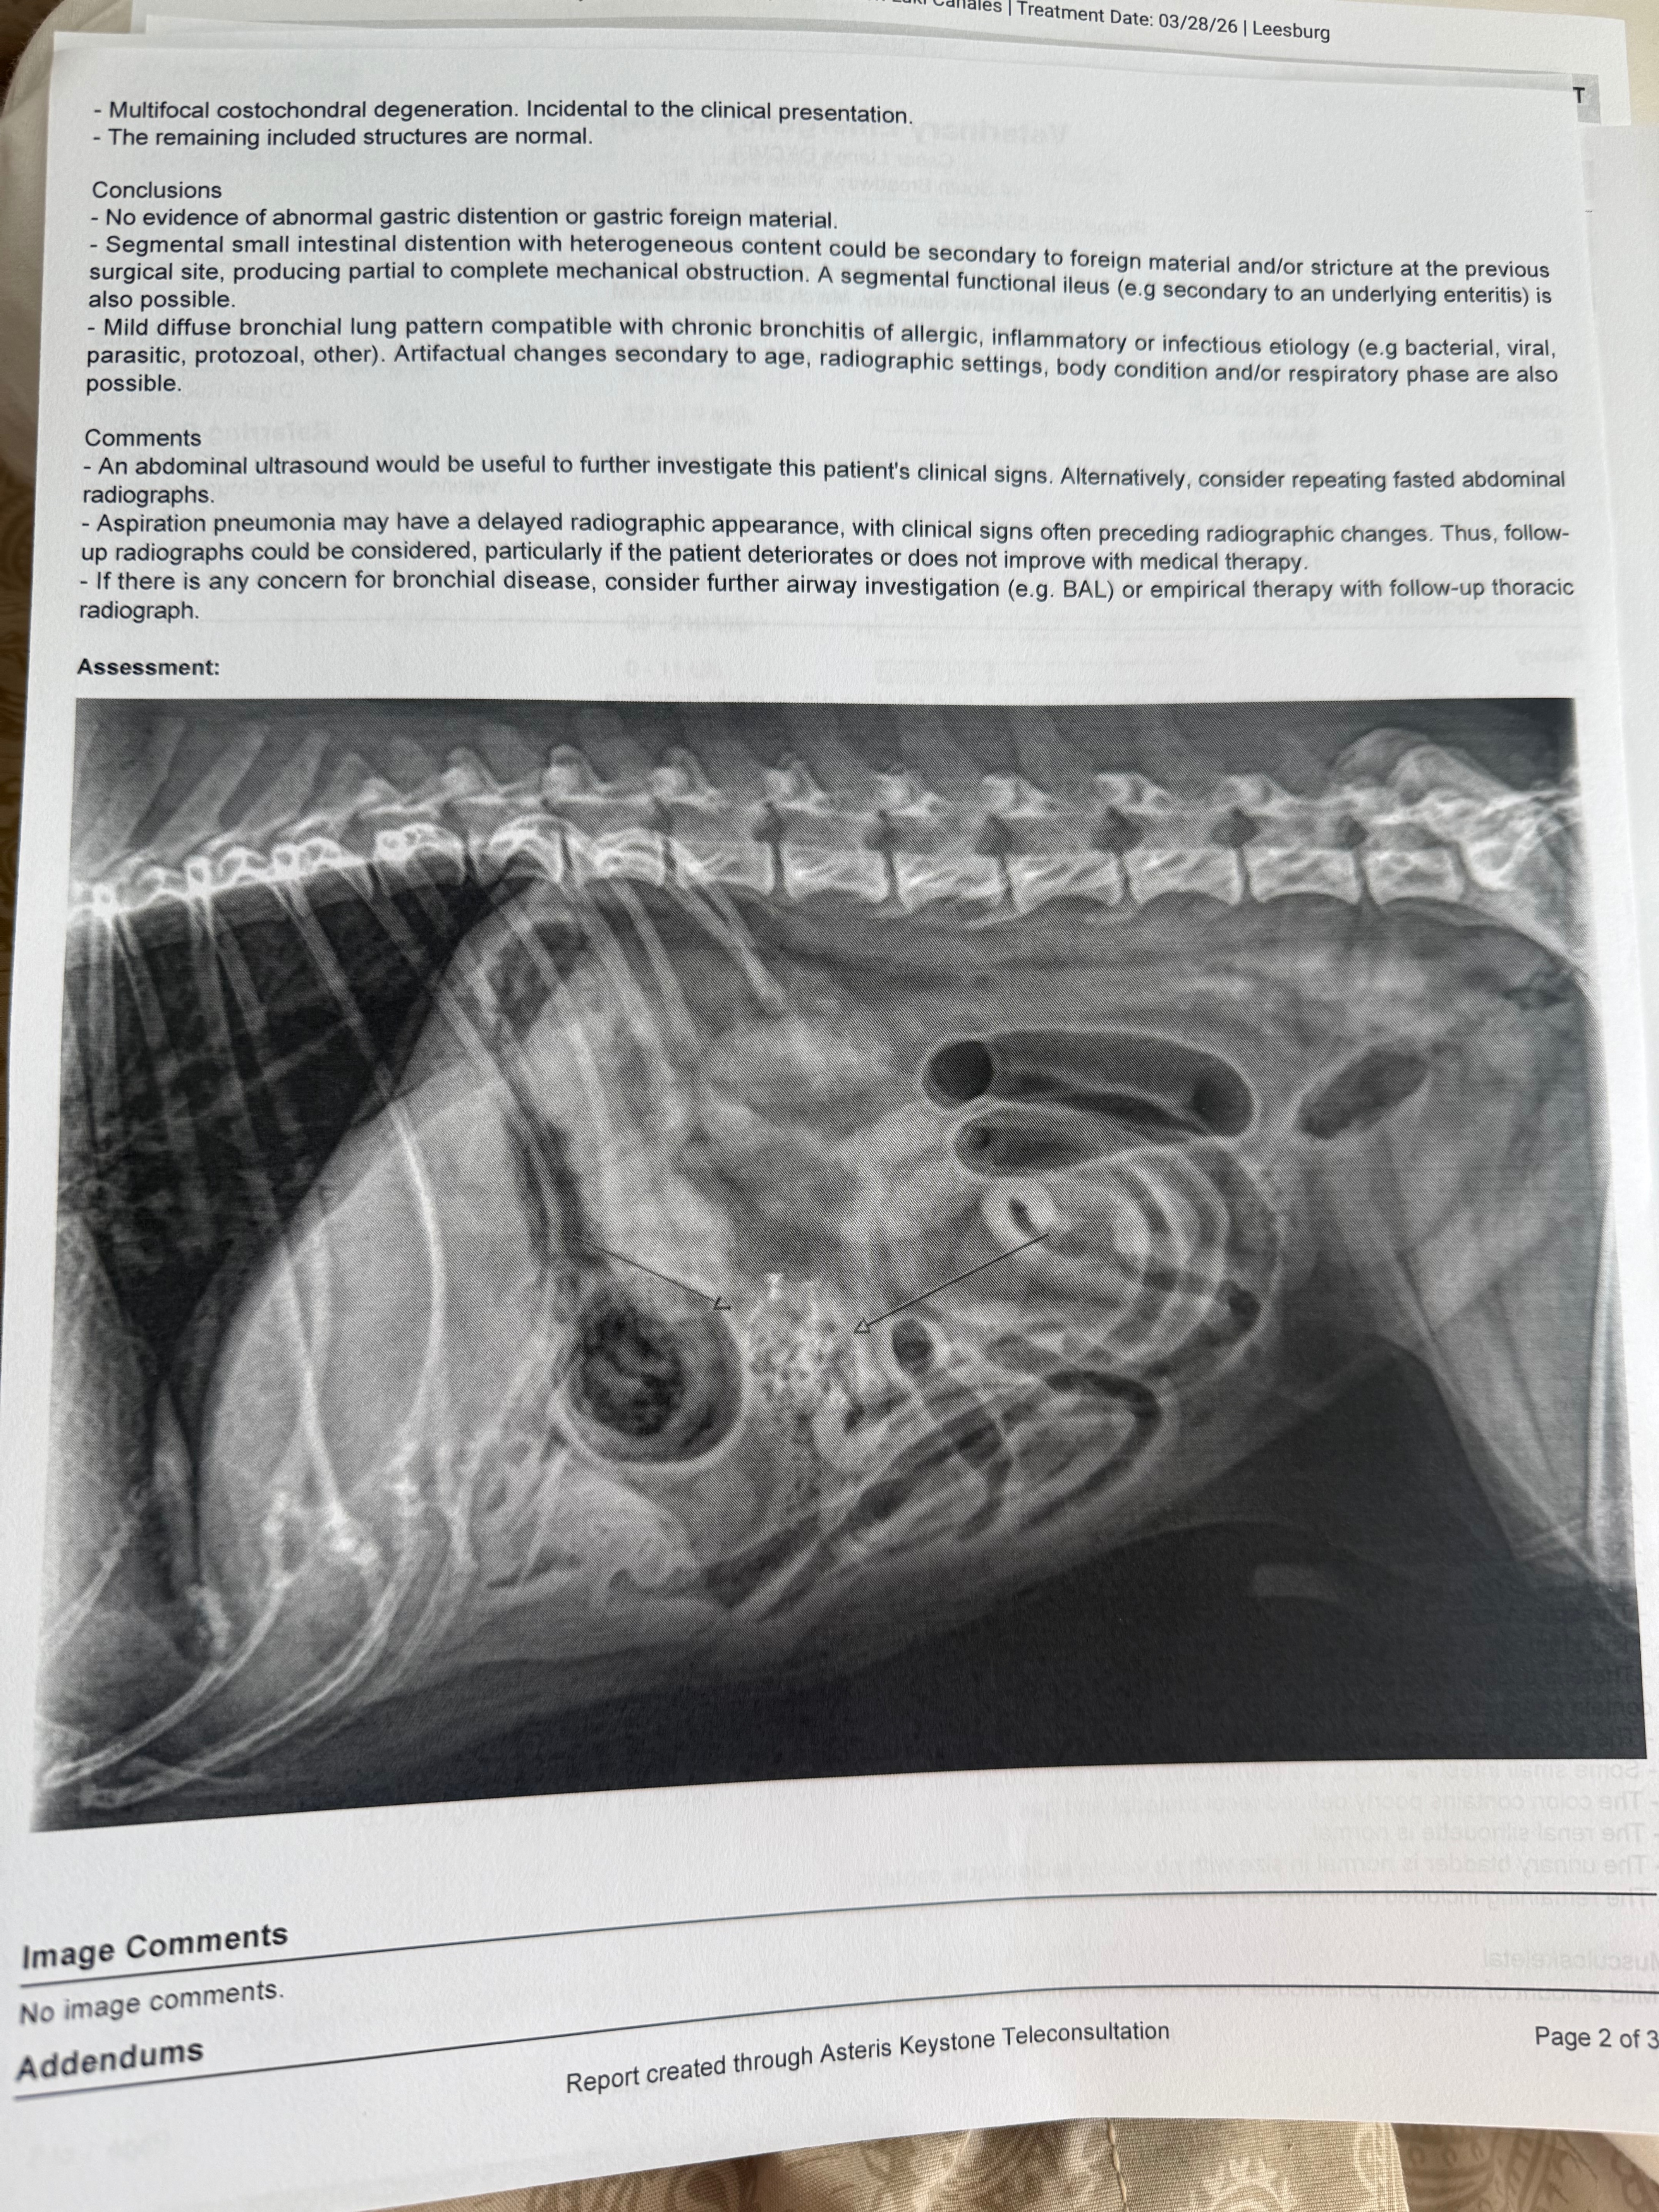

Over the past day, Benny suddenly got very sick—he’s been vomiting, restless, and clearly in pain. After taking him to the vet and getting X-rays done, we were told something really serious: he likely has a blockage in his intestines. The doctor explained it could be caused by something stuck, scar tissue from his previous surgery, or even a mass. Right now, his intestines are swollen with fluid and gas, which means things aren’t passing through like they should.

This situation is urgent. If it’s a full blockage, he may need emergency surgery to survive. Even if it’s partial, it can quickly become life-threatening. The next step is an ultrasound and possibly surgery, but the costs are more than I can afford right now.